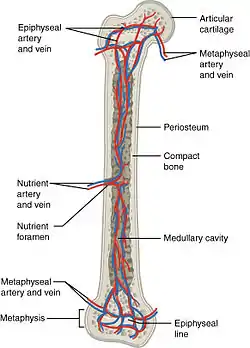

The blood supply to long bones, here with nutrient arteries labeled. | |

The nutrient artery (arteria nutricia, or central artery), usually accompanied by one or two nutrient veins, enters the bone through the nutrient foramen, runs obliquely through the cortex, sends branches upward and downward to the bone marrow, which ramify in the endosteum–the vascular membrane lining the medullary cavity–and give twigs to the adjoining canals. Nutrient arteries are the most apparent blood vessels of the bones.[1]

All bones possess larger or smaller foramina for the entrance of the nourishing blood-vessels; these are known as the nutrient foramina, and are particularly large in the shafts of the larger long bones, where they lead into a nutrient canal, which extends into the medullary cavity (bone marrow cavity).[2]